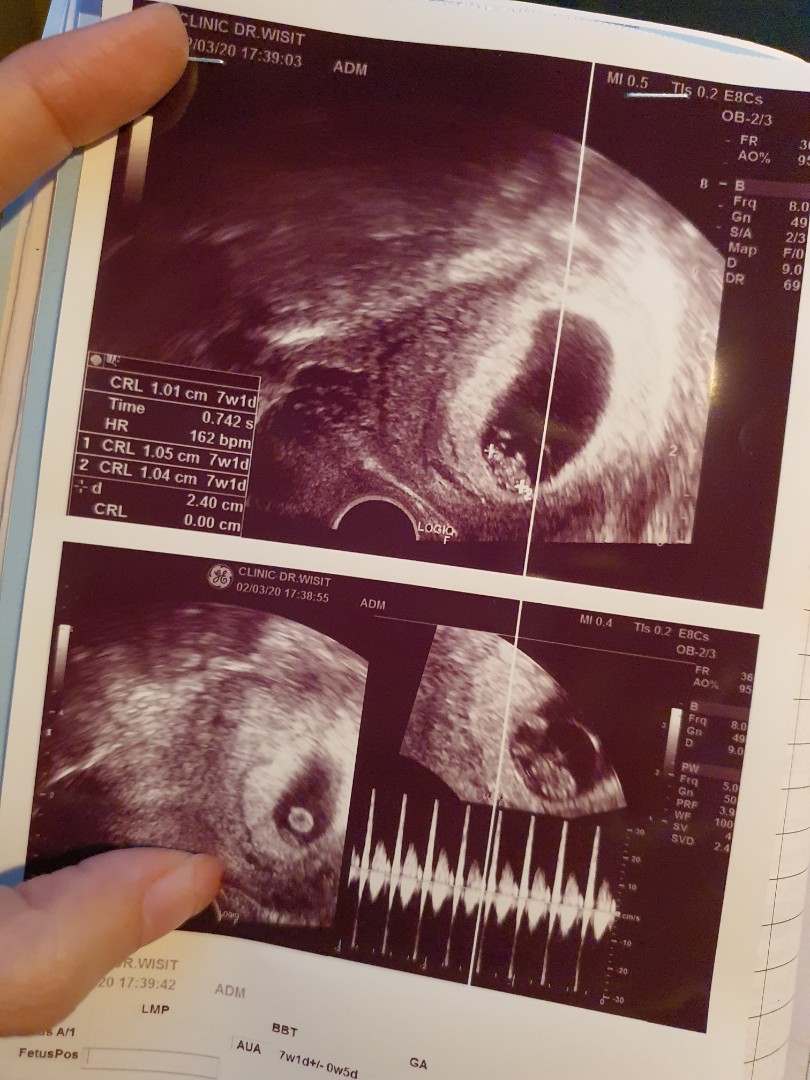

7w1d ได้ยินชัดปกติขึ้นค่ะ ได้ยินครั้งแรกตอน 5wks แต่เต้นช้า เลยได้ยาเหน็บกันแท้งมาช่วย